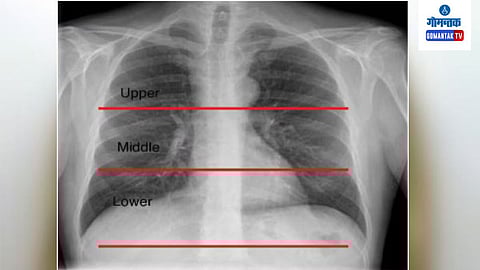

हे एक्स रे चे नवीन मॉडेल व्यक्तीच्या वयाबरोबरच उच्च रक्तदाब आणि ‘क्रॉनिक ऑब्स्ट्रक्टिव्ह पल्मोनरी डिसीज’ सारख्या फुफ्फुसांच्या आजारांविषयीही सूचित करू शकते. कृत्रिम बुद्धिमत्तेवर आधारित एक्स रेच्या मॉडेलने वैद्यकीय प्रतिमा प्रणालीत झेप घेतली असून आजारांचे लवकर निदान होऊन वेळीच उपचार करण्याचा मार्गही मोकळा झाला आहे.

संशोधकांनी ३६,०५१ व्यक्तींचे ६७,१०० एक्स रे काढून कृत्रिम बुद्धिमत्तेवर आधारित मॉडेल विकसित केले. यावेळी या एक्स रेने वर्तविलेला वयाचा अंदाज व व्यक्तीचे कालानुक्रमानुसार किंवा प्रत्यक्षातील वय यात नजीकचा सहसंबंध असल्याचेही संशोधकांना आढळले.

कृत्रिम बुद्धिमत्तेवर आधारित एक्स रेने वर्तविलेले वय जेवढे अधिक तेवढे संबंधित व्यक्तीला वरील आजार होण्याची शक्यता अधिक, असे संशोधकांनी स्पष्ट केले.

कृत्रिम बुद्धिमत्तेवर आधारित एक्स-रे केवळ शरीरातील अवयव व हाडांची स्थितीच दर्शवीत नाही तर तो वय तसेच दीर्घायुष्याबाबत अंदाज वर्तविण्यासाठीही उपयुक्त ठरू शकतो. हे तंत्रज्ञान अधिक विकसित करून जुनाट आजारांच्या तिव्रतेचा तसेच आयुर्मानाचा अंदाज घेण्यासाठी ते वापरण्याचे आमचे उद्दिष्ट आहे. - यासुहितो मितसुयामा, संशोधक